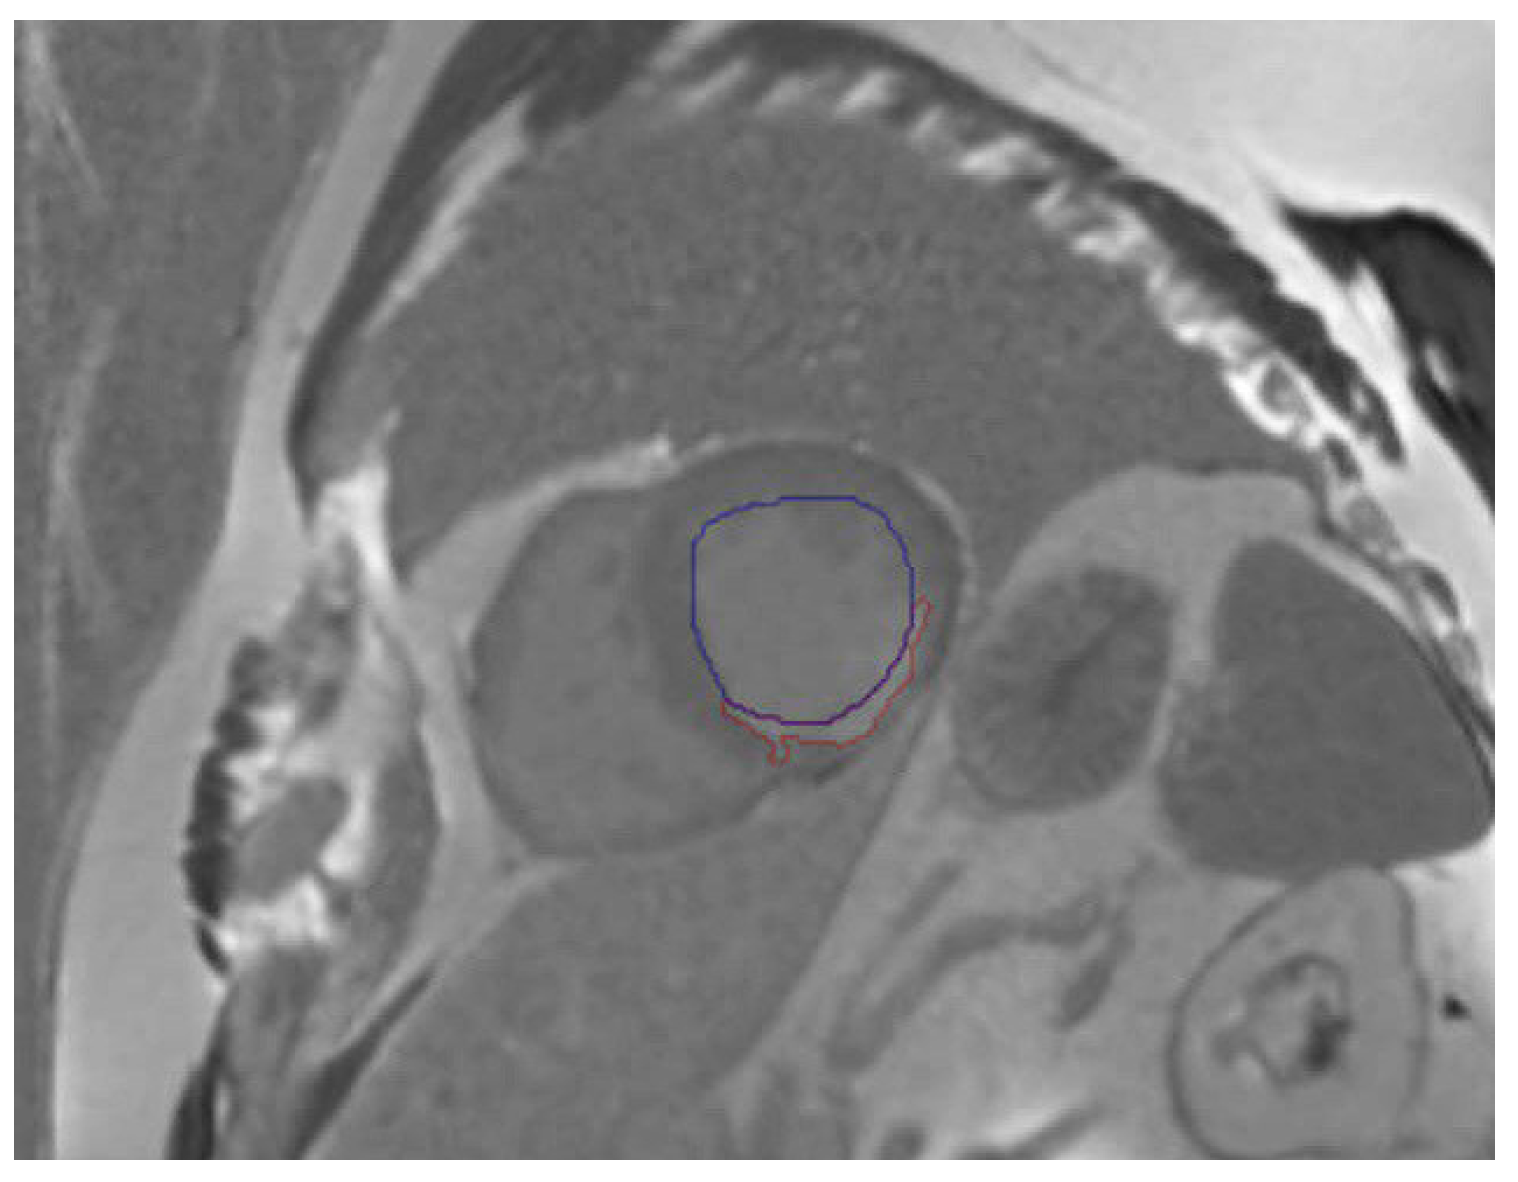

2.5. Evaluation

3.4. Best Model Further Results